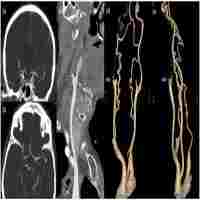

Management of acute tandem occlusions: Stent-retriever thrombectomy with emergency stenting or angioplasty

| Abstract | ObjectiveTo compare outcomes following intracranial stent retriever-based intracranial thrombectomy (SRT) with emergency extracranial internal carotid artery (EICA) stenting or angioplasty alone in patients presenting with acute stroke due to tandem occlusions of the ICA.MethodsConsecutive patients with acute anterior tandem occlusion who received an endovascular intervention within 6h of symptom onset between January 2013 and June 2016 were included in this prospective study. Demographic, radiological, procedural and clinical outcome data were compared between the stenting and the angioplasty alone groups.ResultsOf the 37 patients eligible for the study, 18 had angioplasty alone and 19 underwent stent placement. Successful recanalization rate was statistically significantly higher in the stenting group than in angioplasty alone group (74% vs. 39%) and although not statistically significant, more patients in the stenting group than in the angioplasty alone group had favourable outcomes (63% vs. 50%). There was no significant difference between groups in rates of symptomatic intracranial haemorrhage (SICH), cerebral herniation or mortality.ConclusionThis study in a small sample size suggests that among patients with acute anterior tandem occlusion, SRT with EICA stenting tended to achieve higher recanalization and improved clinical outcomes at three months compared with SRT and angioplasty alone with a similar rate of SICH and mortality. |